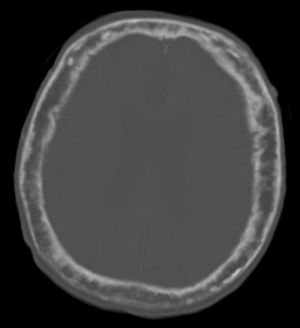

Pagets skull.jpg

"This 92 year-old male patient presented for assessment of sudden inability to move half his body. An incidental finding was marked thickening of the calvarium. The diploic space is widened and there are ill-defined sclerotic and lucent areas throughout. The cortex is thickened and irregular. The findings probably correspond to the 'cotton wool spots' seen on plain films in the later stages of Paget’s disease."